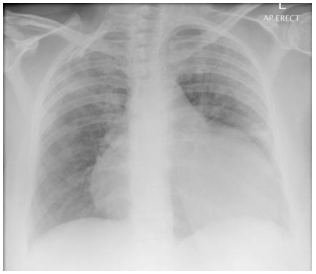

Homem, 60 anos, portador de diabetes mellitus e insuficiência

renal crônica em hemodiálise três vezes por semana há dois anos.

Na última semana, após faltar a duas sessões de diálise, evoluiu

com dispneia aos pequenos esforços e dor torácica pleurítica.

Considerando sua radiografia de tórax (acima), assinale a opção que apresenta um possível achado no seu exame físico.